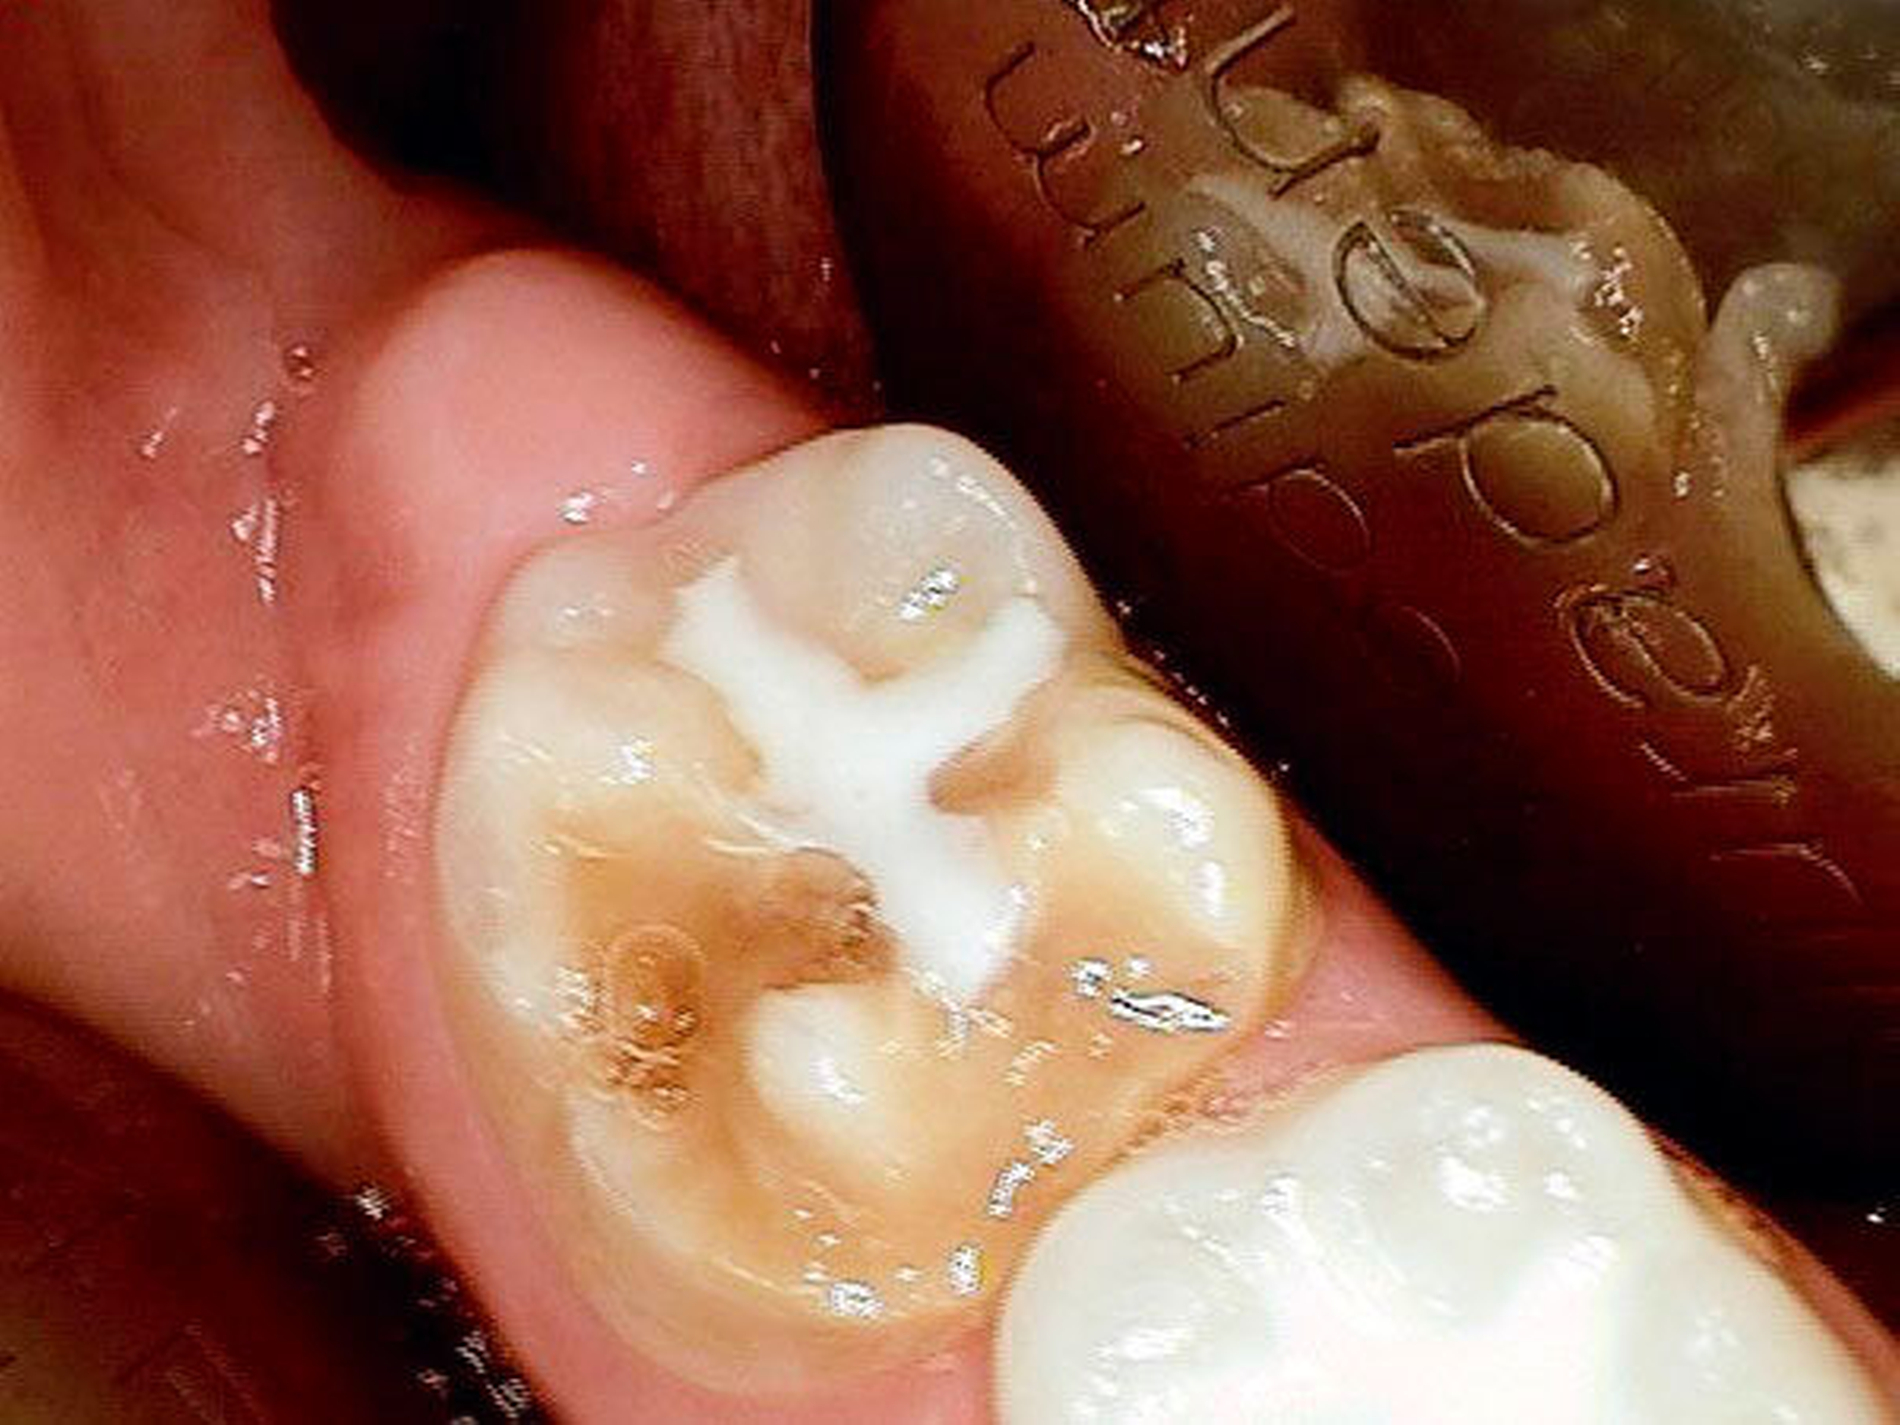

Aufgrund der noch nicht eindeutigen Gebissentwicklung des Patienten und der Tendenz zum Engstand wurde in Absprache mit den Eltern, dem Hauszahnarzt und dem Kieferorthopäden die Entscheidung getroffen, dass die stärker betroffenen und sehr empfindlichen Zähne 26, 36 und 46 mit Stahlkronen versorgt und Zahn 16 neu versiegelt werden sollte (Abbildungen 6 bis 8).

Stahlkronen der Sechsjahrmolaren sind ähnlich anzuwenden wie die etwas besser bekannten Stahlkronen im Milchgebiss. Im Gegensatz hierzu ist jedoch auf eine möglichst schonende Präparation zu achten, um genügend Substanz für die spätere definitive Versorgung zu erhalten, die bis zum 15. Lebensjahr erfolgen sollte.

Die konfektionierten Kronen kommen in den Fällen zur Anwendung, wenn die Zähne zumindest über einen gewissen Zeitraum erhalten werden sollen, die Defekte jedoch zu groß für die Füllungstherapie sind.

Leider ist die Präparation der Sechsjahrmolaren oft zeitraubender und geht meist mit erheblichem Substanzverlust einher. Nach versuchter schonender tangentialer Präparation mesial und distal sowie Reduktion der Höhe um circa 1,5 mm wird die entsprechende Kronengröße ausgewählt. Diese kann noch durch Kürzen oder Biegen des Randes individualisiert werden. Wichtig ist es, vor dem definitiven Einsetzen der Kronen den korrekten Sitz mittels Röntgenbild zu überprüfen. Bedingt durch das Fehlen eines basalen Schmelzwulstes lässt sich die Konfektionskrone trotz eines elastischen Federrandes auf dem konisch beschliffenen Zahn nur schwer fixieren. Störungen der Okklusion sind die Norm (noch unproblematisch im beginnenden Wechselgebiss), ein exakter Randschluss ist praktisch nicht zu erreichen. Insbesondere interdental, am Übergang zwischen Krone und Zahn, sind in jedem Fall Retentionsnischen vorhanden, die die Ansammlung von Plaque begünstigen. Folgeproblem ist Sekundärkaries und eine dauerhafte Irritation des marginalen Parodontiums. Verbleiben die Kronen über das 15. Lebensjahr hinaus im Mund, muss mit zum Teil erheblichem Knochenabbau gerechnet werden!